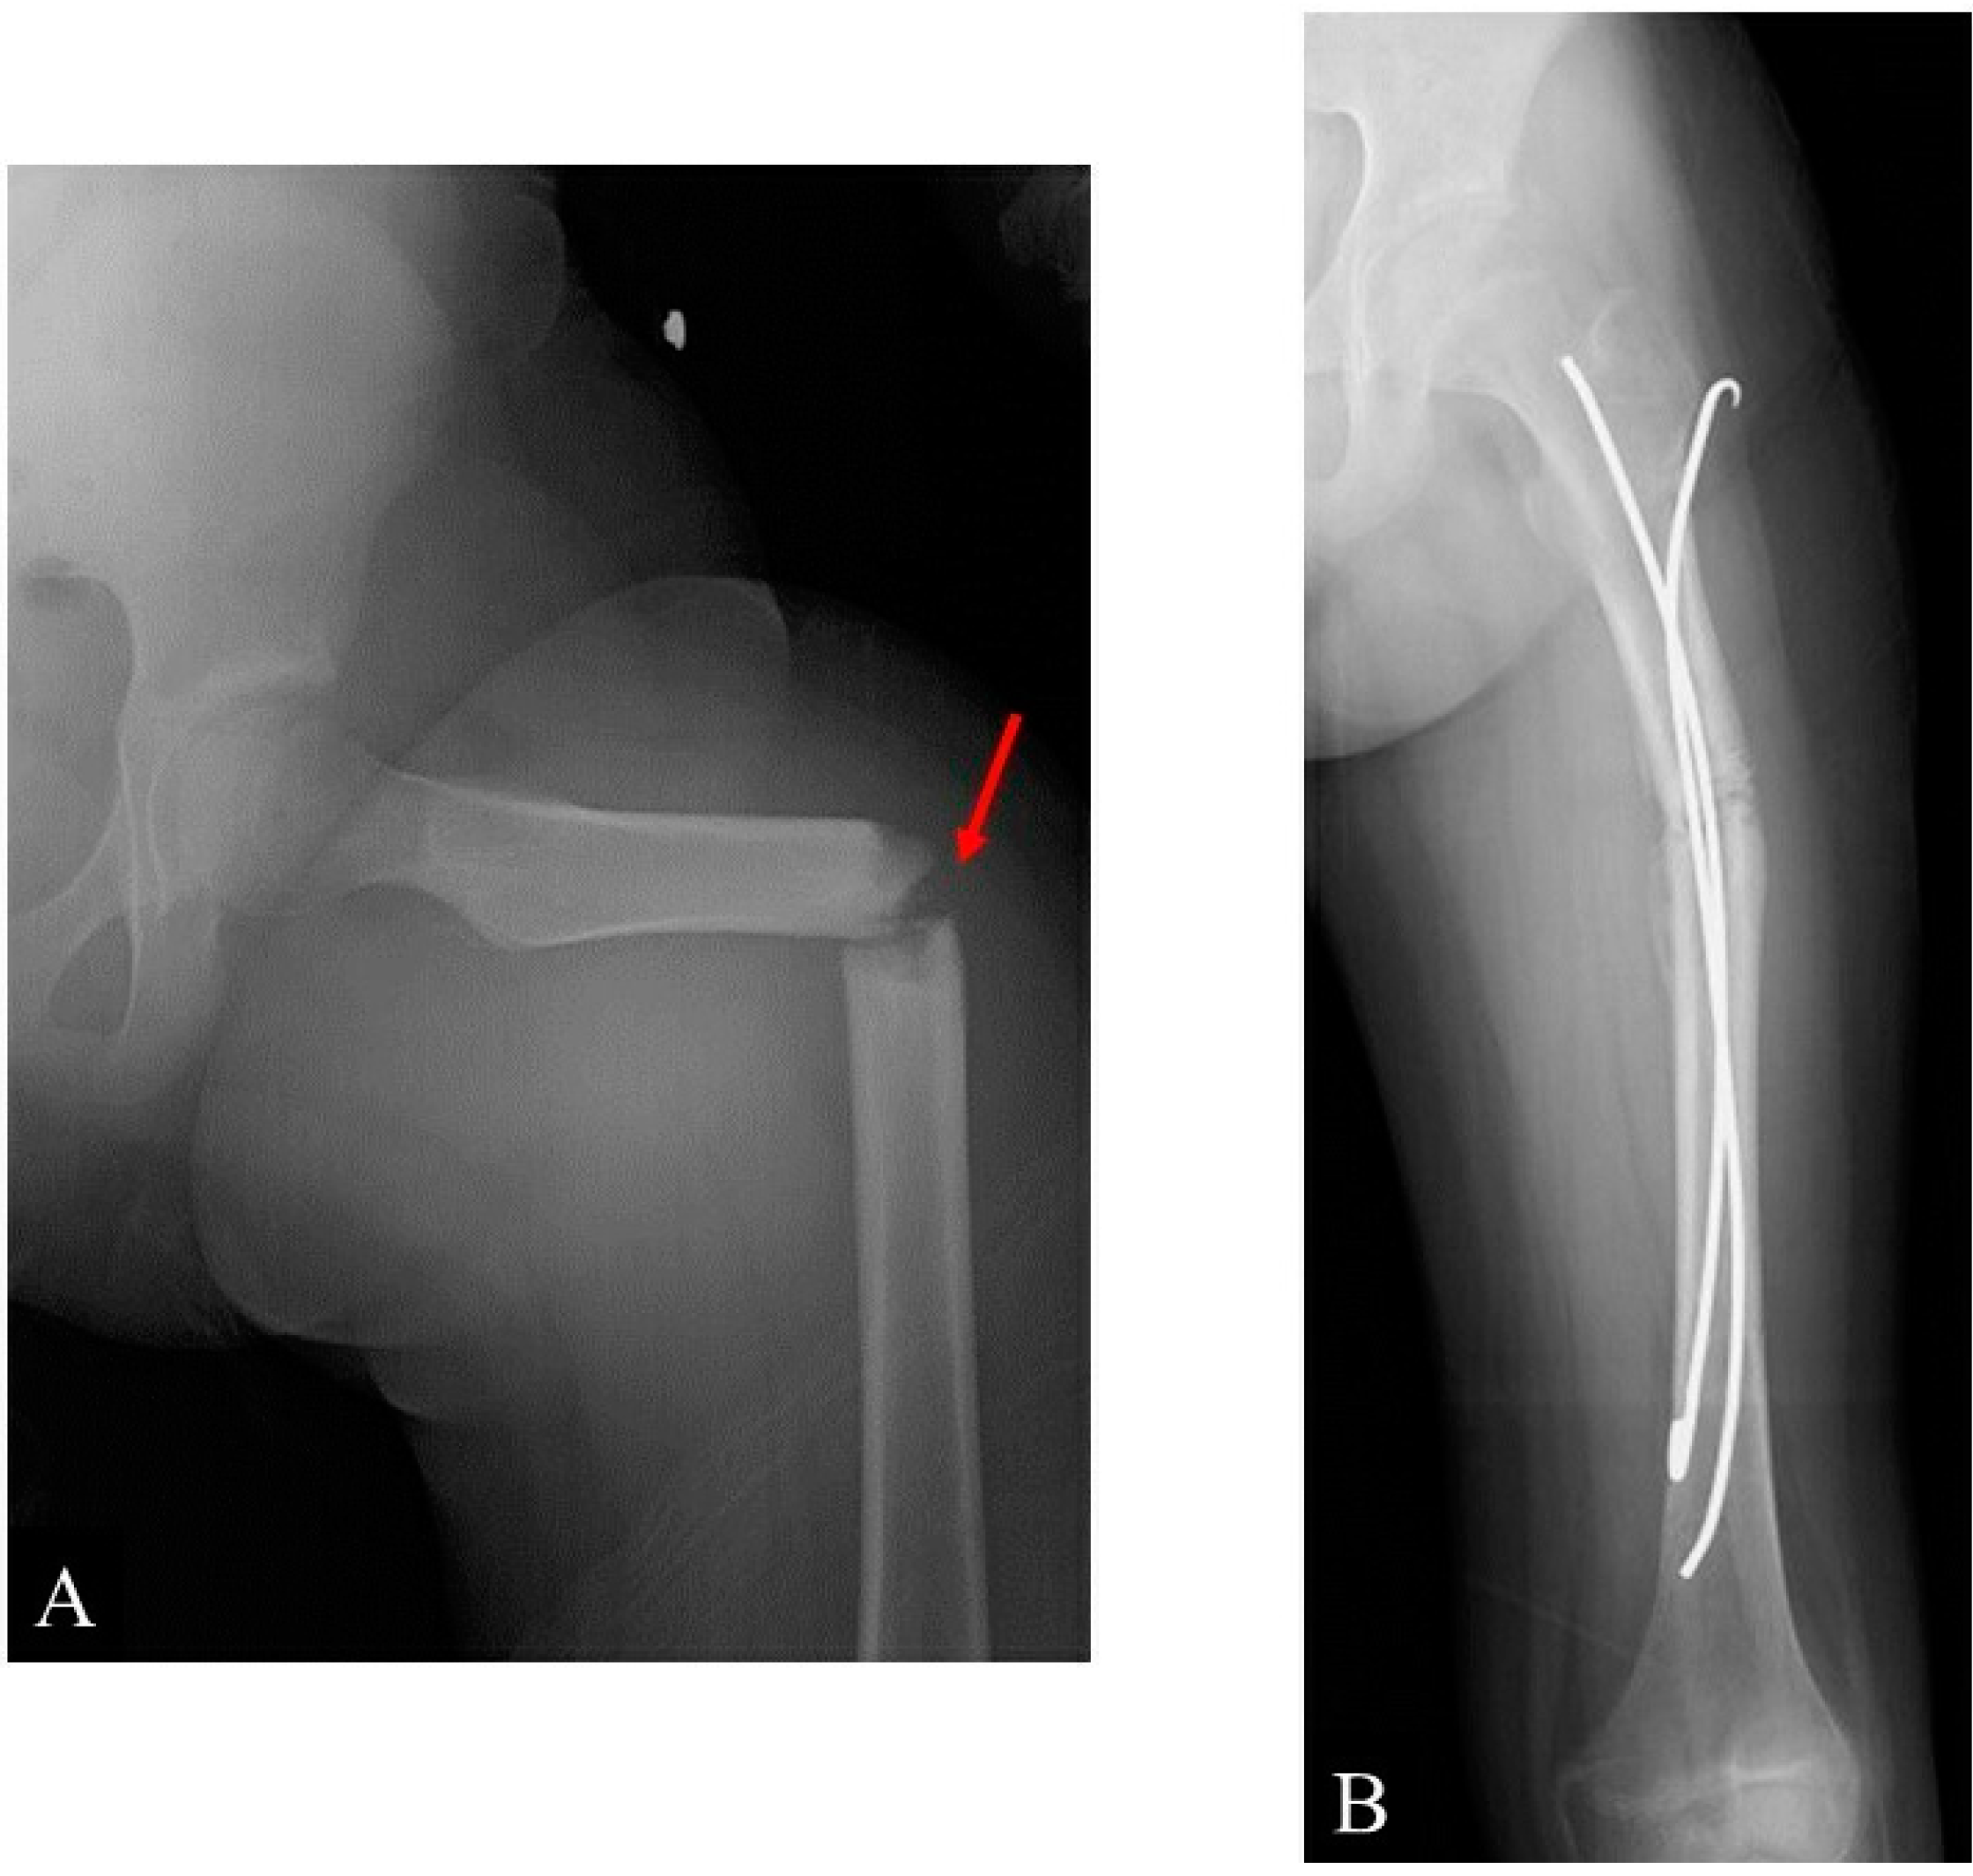

2. Case Presentation

- Tumor resection and femoral stabilization, according to results of FEA.